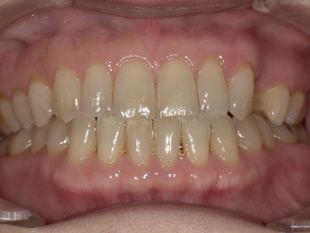

▼ 治療後(ノンクラスプデンチャー装着)

-

歯ぐきの色に馴染む樹脂で金具ゼロの自然な見た目

厚みが薄く、軽いため痛みほぼゼロの快適さ

義歯のフィット感が高く、噛む力も安定

口元がふっくらし、見た目・印象が10歳以上若返る

患者様からは、

「友達にも入れ歯だと気づかれなかった!」

「痛くない入れ歯は初めてで驚きました」

という喜びの声をいただきました。